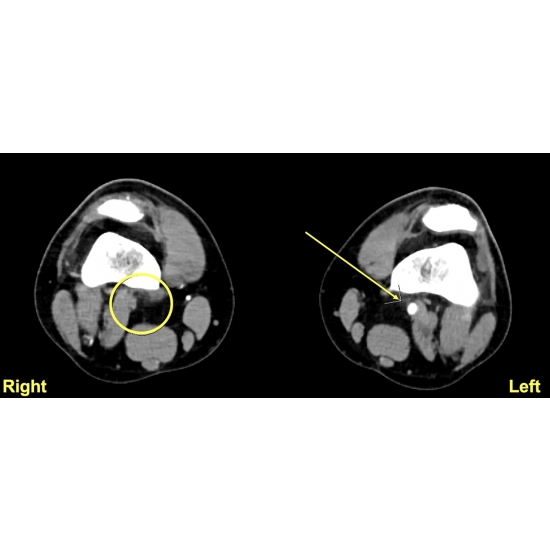

| Poor Perfusion Or Elevated Pressures? An Exertional Lower Limb Pain Conundrum - Page #3 | |||